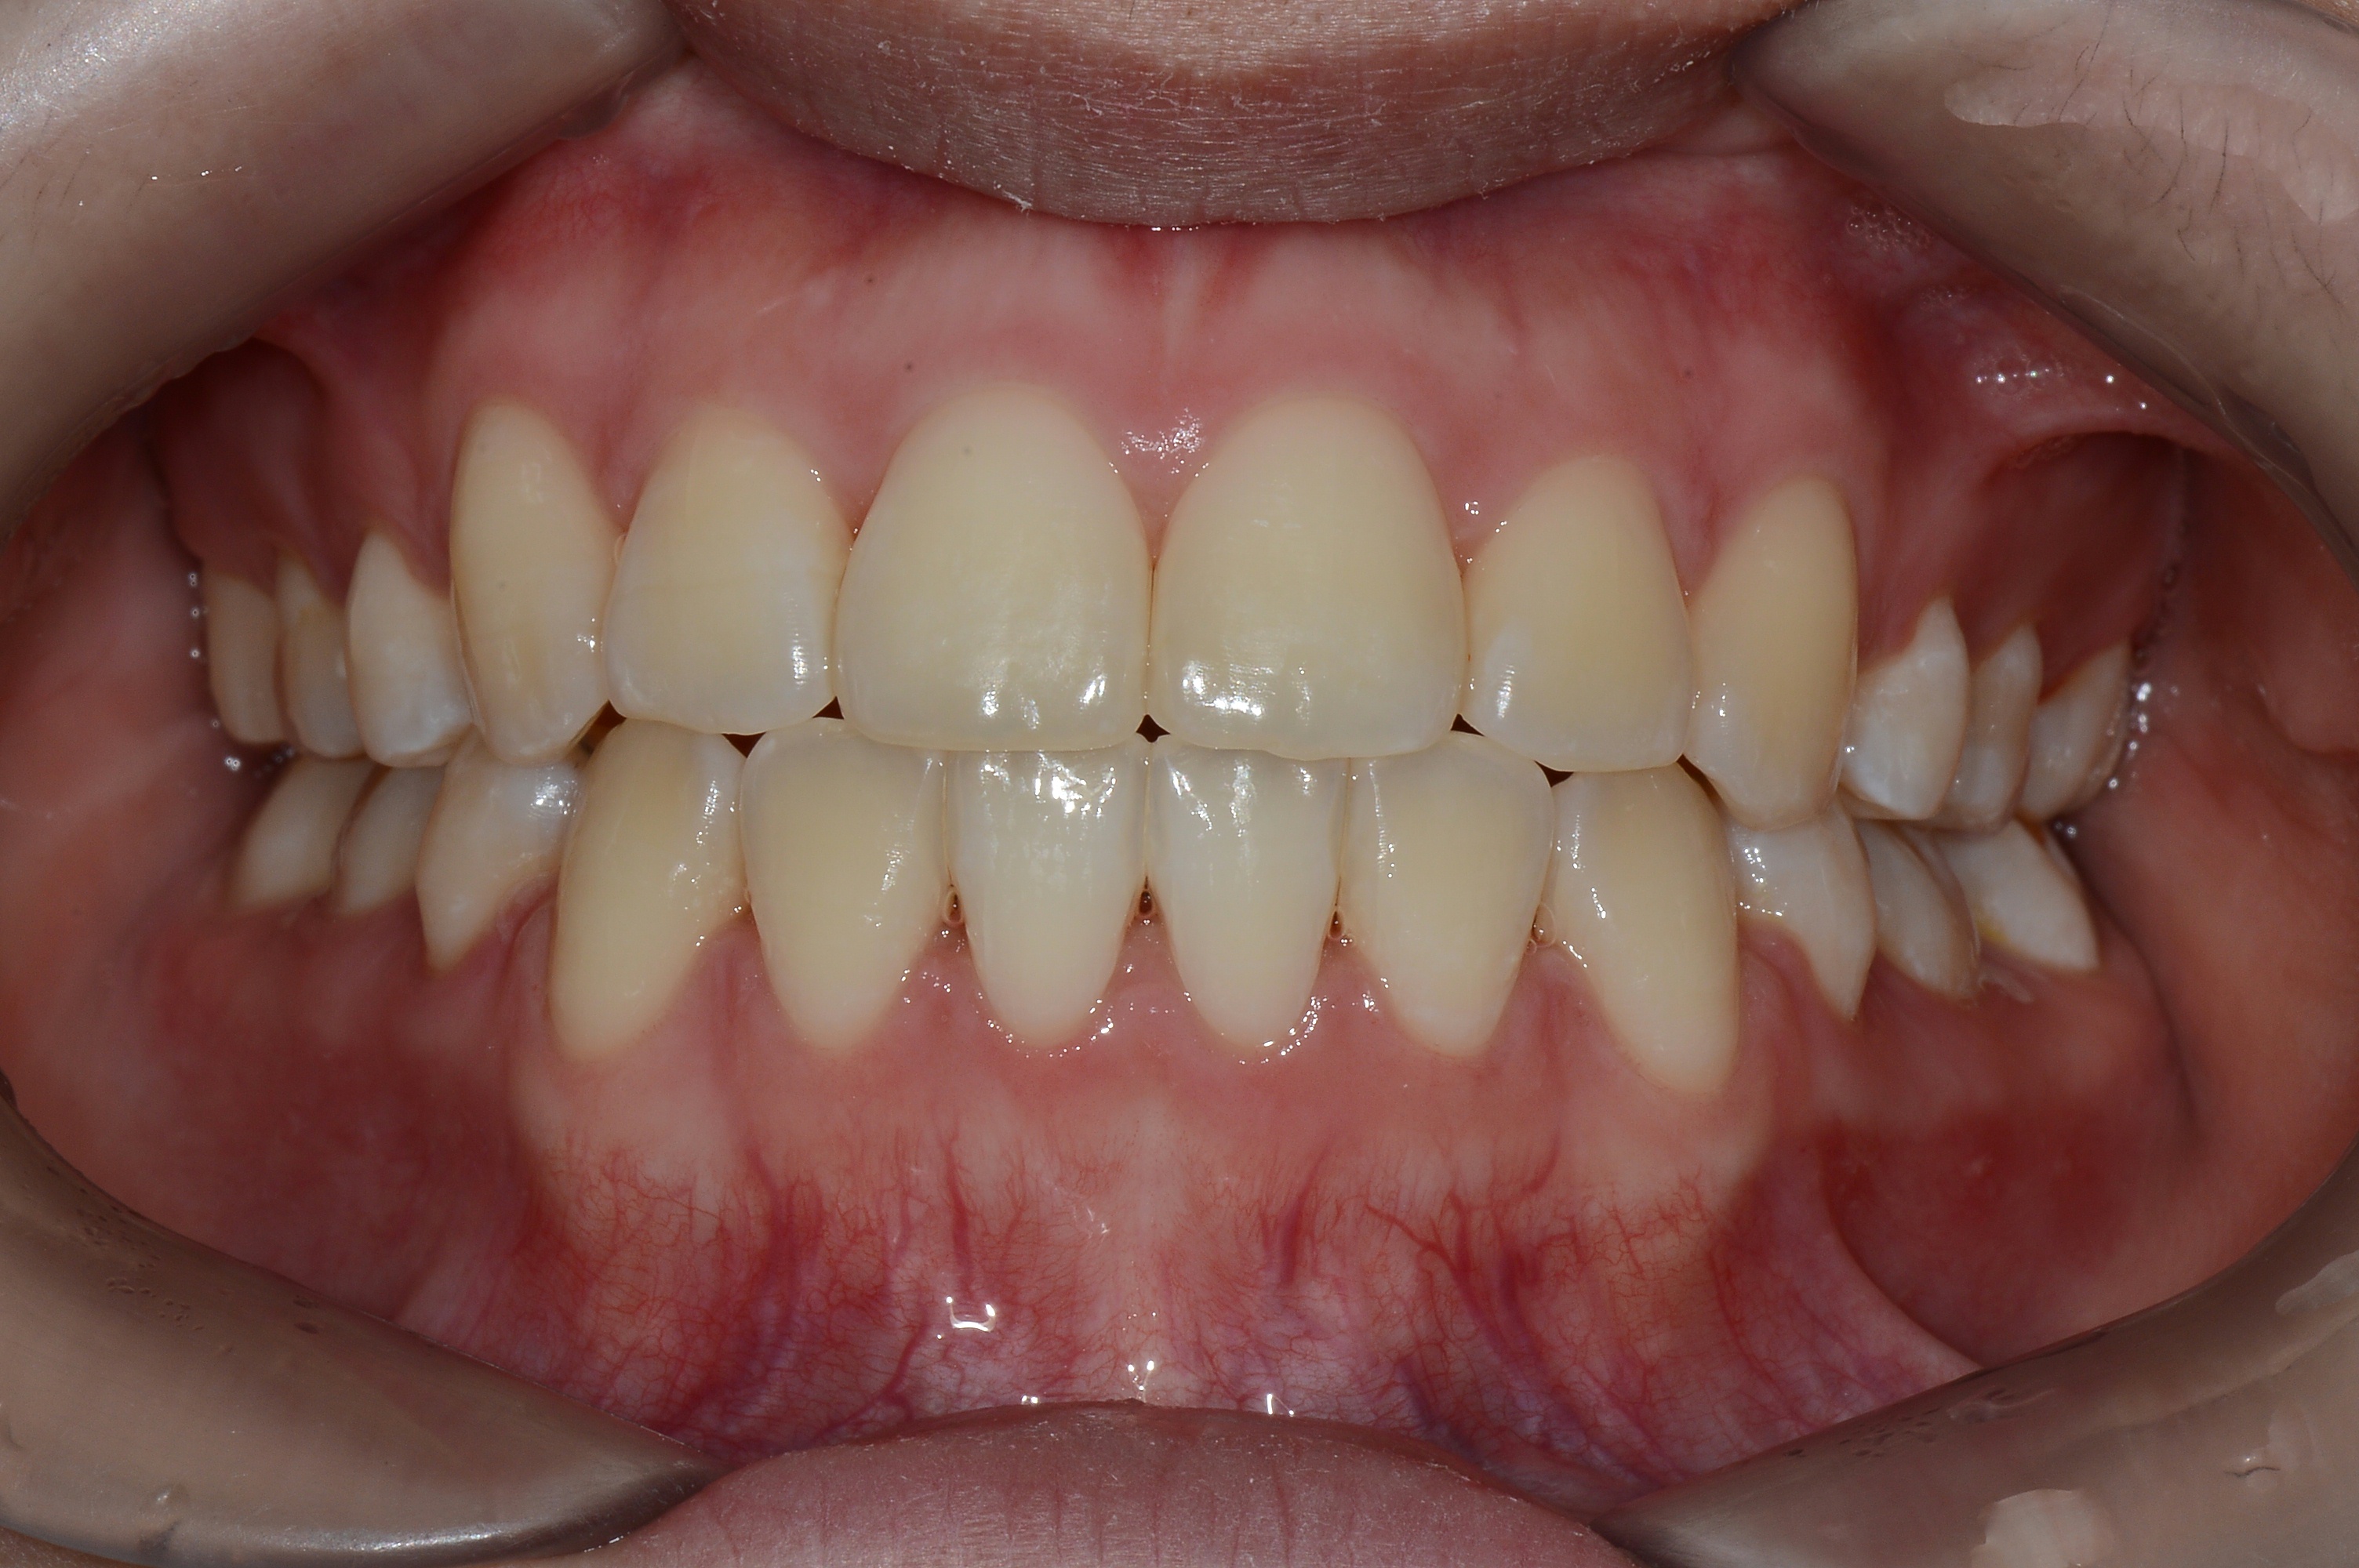

치료 후 사진입니다.